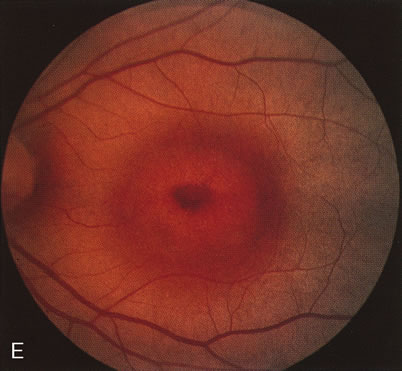

Fluorescein angiography highlights observable fundus findings. In patients with a golden reflex the FA is normal (Fig. 2E, F) or shows a mild transmission hyperfluorescence.7